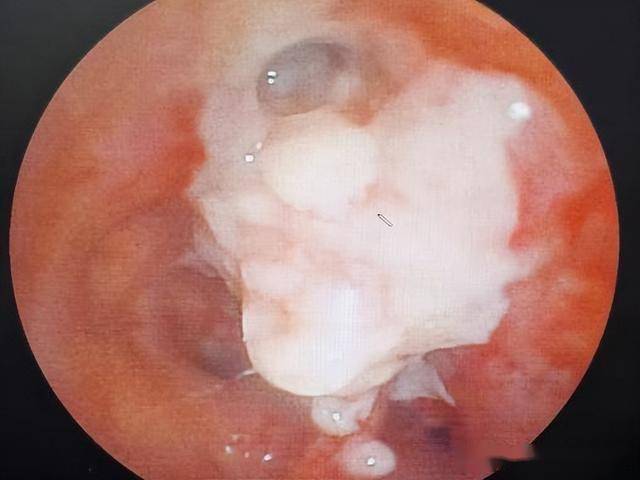

⋄ 支气管镜下新生物电切术。

治疗前:右主支气管完全堵塞

治疗后:右上支气管开通

“海” - 腔内治疗(管腔内):针对突出生长在气管、支气管管腔内部的肿瘤或肉芽肿等。

● 核心思想:从管腔内部对病变进行“削除”、“掏空”或“烧灼”。

● 常用技术:高频电刀/圈套器、氩等离子凝固、激光、冷冻治疗、腔内放射治疗。